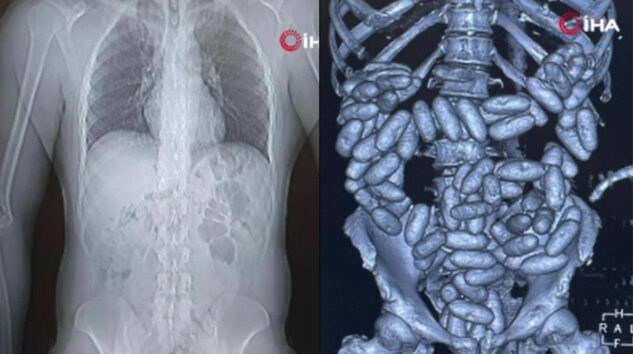

Cihazda, şüpheli yoğunluk tespit edilmesi üzerine zanlılar, muayene edilmek üzere hastaneye götürüldü. Burada yapılan tetkikler ve röntgen kontrollerinde, yolcuların sindirim sisteminden daralı ağırlığı 3 kiloyu bulan 360 kapsül içinde eroin tespit edildi.